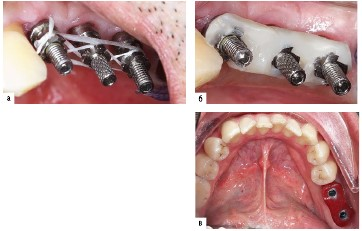

image

Рис. 2.9.4. Съемный протез на имплантатах на верхней челюсти и несъемный - на нижней челюсти при полном отсутствии зубов: а, б - имплантаты в полости рта; в, г - балка на имплантатах для опоры съемного протеза на верхней челюсти; д, е - металлический каркас на имплантатах для фиксации керамических коронок на нижней челюсти; ж - ортопантомограмма челюстей с балкой и каркасом на имплантатах; з - протезы на имплантатах в полости рта

Имплантаты чаще применяются для несъемных протезов, которые могут быть металлокерамическими, металлопластмассовыми, цельнокерамическими, керамико-керамическими на каркасе из диоксида циркония, а также с использованием стандартных пластмассовых зубов на металлическом каркасе (так называемые условно-съемные протезы) (см. рис. 2.9.4).